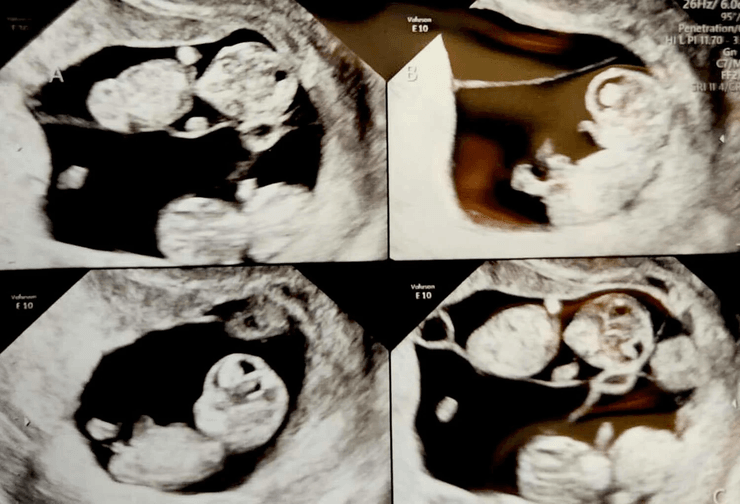

Супруги, у пары родились близнецы, четыре одинаковые дочери, дети, идентичные четверняшки, одинаковые дочери, родила 4 девочки, УЗИ,

Мерседес была всего на седьмой неделе беременности, когда впервые увидела девочек

Мерседес была всего на седьмой неделе беременности, когда, по ее словам, на экране УЗИ появились "четыре маленьких мешочка".